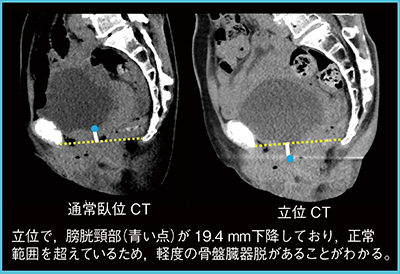

骨盤底の位置は臥位と座位で変化しないとされ,また,立位で骨盤底を評価した研究は,これまでほとんど行われてこなかった。そこで,膀胱頸部と直腸肛門移行部をつなぐライン(PCL)の位置の変化を臥位と立位で比較した。その結果,立位では,膀胱頸部は健常例でも男性で6mm,女性で10mm降下することがわかってきた2)。

図4は,下腹部違和感のある症例である。産婦人科の受診でも原因不明であったが,立位CTでは膀胱頸部が19.4mm下降しており,軽度の骨盤臓器脱があることが明らかとなった。

図4 骨盤臓器脱(70歳代,女性)の早期診断